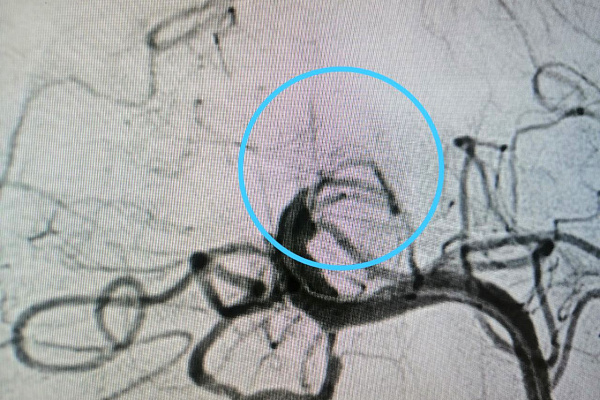

Поэтому следующим этапом оперативного лечения стала ангиопластика. Для неё используется баллонный катетер. Он вводится в сосуд и расширяется под давлением, устраняя стеноз. Как правило, такой «продувки» достаточно для восстановления сосуда в диаметре. Но в данном случае это помогло ненадолго – стенки артерии снова спадались, возвращаясь в прежнее положение. Тогда Максим Бессмертных принял решение об интракраниальном стентировании. Эта операция – из разряда крайних мер. Стентирования внутричерепных артерий при их сужении стараются избегать до последнего из-за высоких рисков.

Сохранить эффект от успешно выполненной ювелирной операции (фото №3) предстояло анестезиологам-реаниматологам. С учётом индивидуальных особенностей пациента они сумели подобрать антиагрегантную и анитикоагулоянтную терапию, чтобы избежать дальнейшего тромбоза стента. Это естественная реакция организма на инородное тело в любом сосуде, которая блокируется соответствующими препаратами.